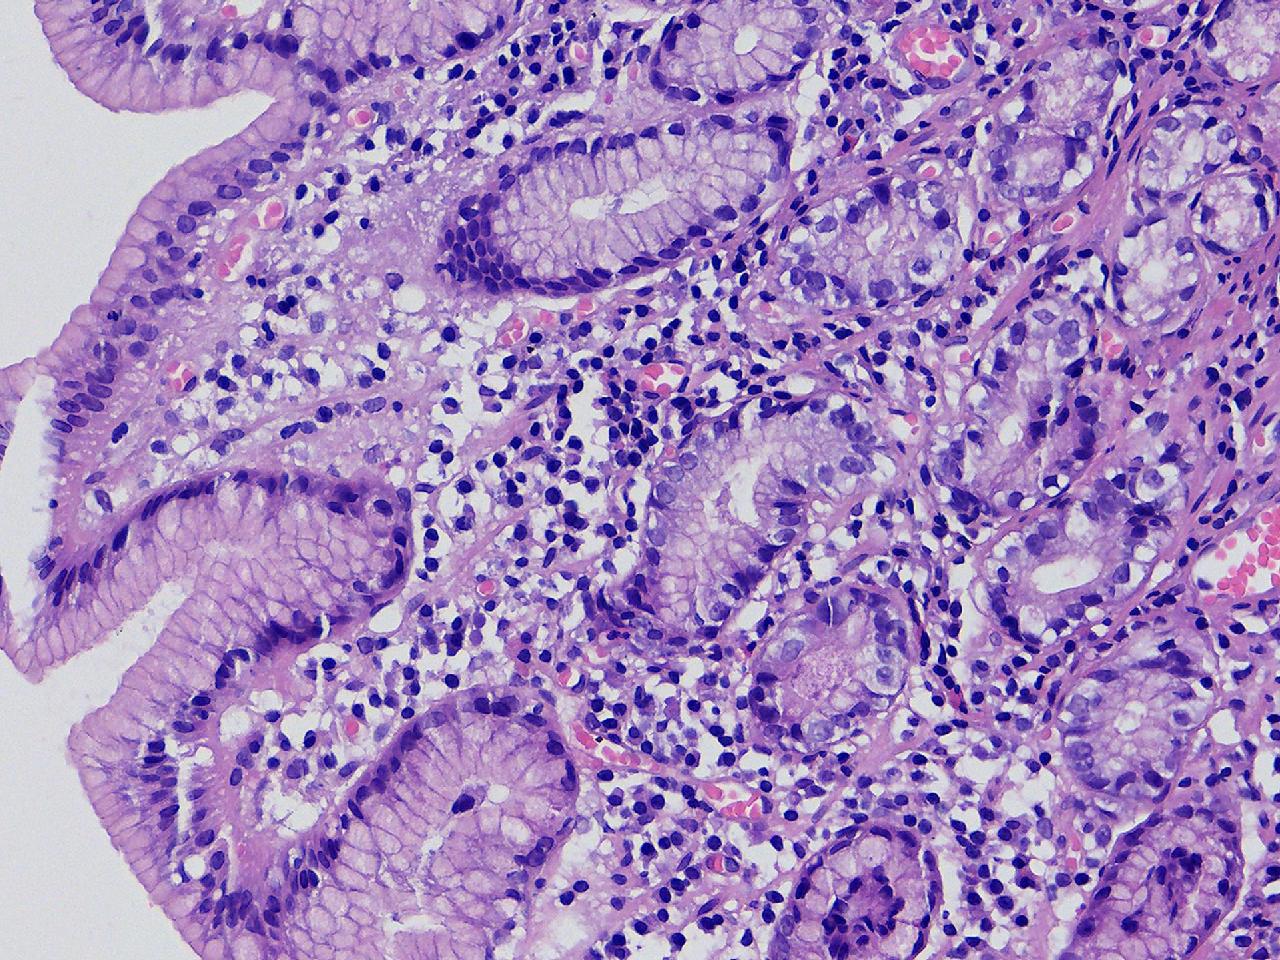

间质内是炎细胞吗?

男,49岁,胃镜活检,胃窦粘膜红白相间,以红为主,后壁见一直径约0.4cm大小片平隆起,表面糜烂,活检1块送检,质软弹性可。

胃窦活检

灰白色不整形软组织1块,直径0.2厘米。

是!还有组织细胞

幽门型粘膜中度慢性炎

是的,主要是淋巴细胞和浆细胞。